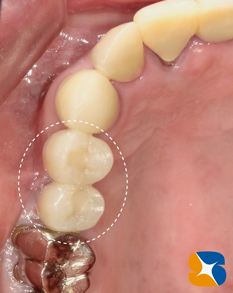

3連結のブリッジを除去すると、手前の歯の根が腐食して、歯も根も溶解していることが判明しました。